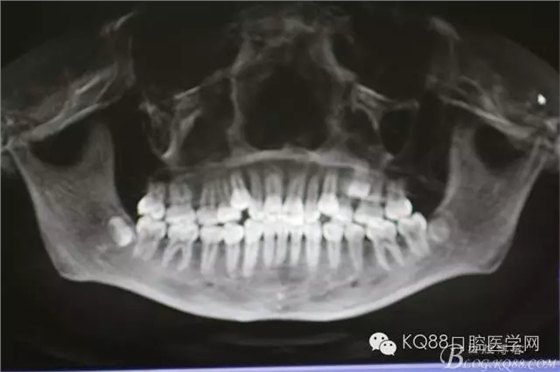

圖3.術前的CBCT檢查:全景片重建影像,25位于24與26牙根的中1/3處。